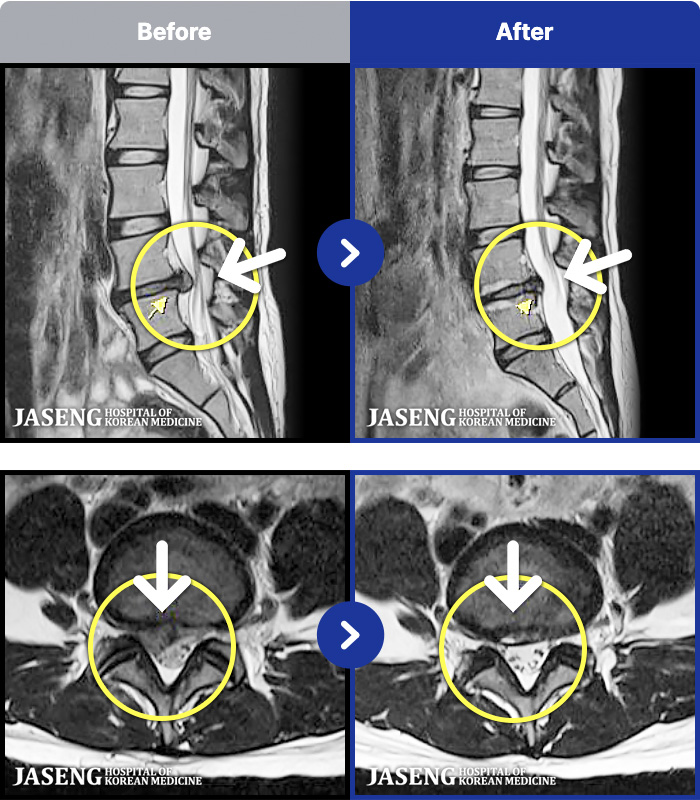

- MRI ġ

MRI ġ

97 MRI ũ ʸ Ȯϼ.